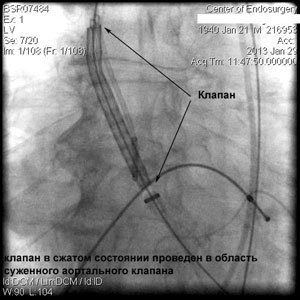

Через прокол (или маленький разрез) в артерии, в сжатом состоянии проводят искусственный клапан, который расширяется при его установке на месте поврежденного аортального клапана. После раскрытия клапан начинает функционировать и восстанавливает полноценную и нормальную работу аорты.